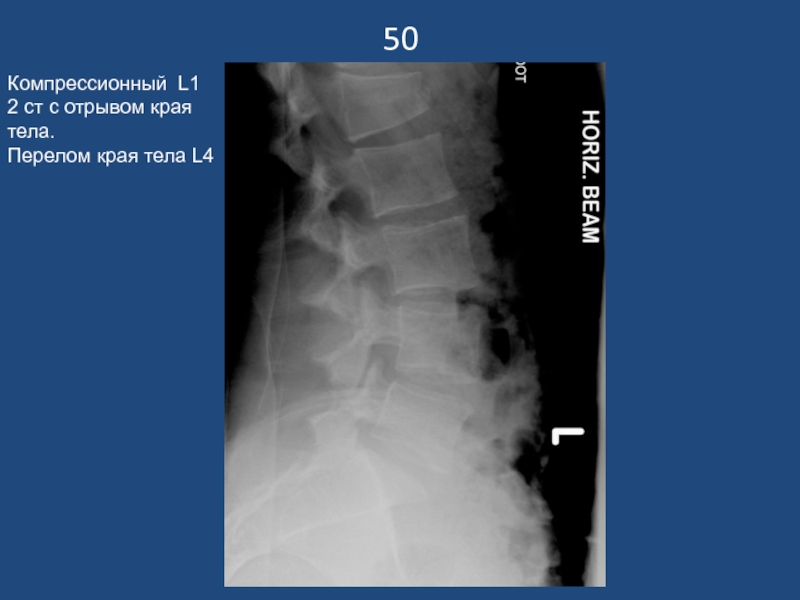

Слайд 5150

Компрессионный L1 2 ст с отрывом края тела.

Перелом края тела

50Компрессионный L1 2 ст с отрывом края тела.Перелом края тела L4